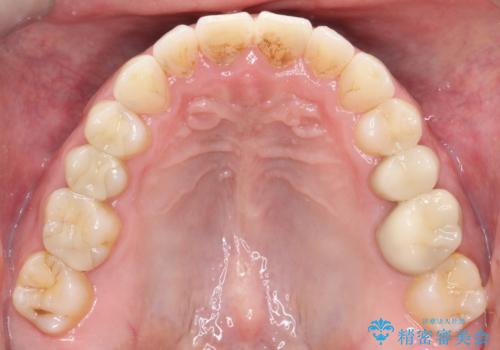

【インビザライン】前歯の隙間を閉じたい

- 前歯の隙間を主訴に来院されました。

マウスピース矯正にて、隙間を綺麗に閉じることができ満足していただきました。

前歯の隙間を閉じる際は、前歯部の突き上げが懸念されるため、適切な治療計画が必要となります。